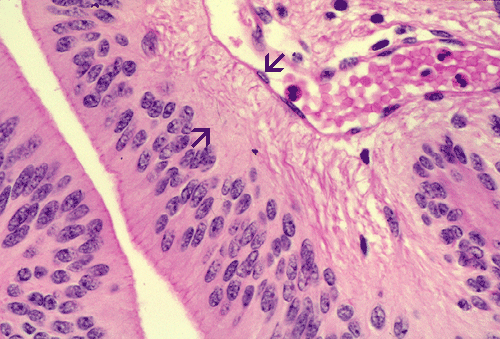

The histopathology of the tumor is fairly similar in different parts of the of the tumor and the papillary structures are the obvious (Panel A). On medium and high magnification (Panel B and C respectively), the cores of the papillary structure is composed of thin walled blood vessels. The tumor cells appear to appear in a pattern reminiscent of the pseudocolumnar arrangement of the respiratory respiratory epithelium except that no basement membrane can be identified. The cores are also not composed of collagenous tissue but by fibrillary process that appear to extends from the nuclei. A zone of hyponuclear area is present between the nuclei and the vascular channels (delimited by arrows in Panel C). No cilia are noted on the surface epithelium and no mucin production is noted. The cytoplasmic border is very indistinct. The nuclei appear to be rather bland appearing and mitotic figures are not readily seen. There is neither endothelial proliferation nor necrosis.

Papillary ependymoma, as illustrated in this case, is a rare variant. These tumors typically appear as papillary fronds covered by multilayered ependymal tumor cells. The most superficial layer may have epithelium-like surfaces similar to those of ependymal rosettes. These tumors must be distinguished from metastatic papillary carcinomas and choroids plexus tumors. One salient feature is that papillary ependymomas have no basement membrane. The superficial epithelial tumor cells merge imperceptibly with the underneath tumor cells. Papillary ependymoma can express cytokeratin. It is not rare to see focal papillary formation in an otherwise classic ependymoma. However, tumors composed predominantly of papillary structure as illustrated in this case is uncommon.